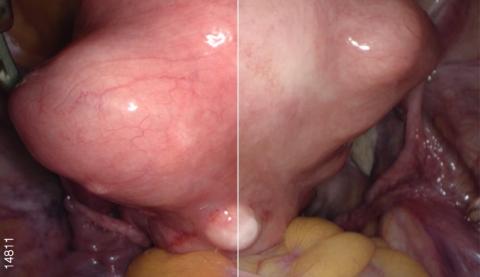

Видеоэндоскопическая система OLYMPUS VISERA 4K UHD обладает высококачественным изображением 4K и технологией узкоспектральной визуализации изображения NBI. Высокое разрешение позволяет визуализировать малейшие изменения в структуре тканей для ранней диагностики очагов воспаления и опухолей. Чем выше разрешение изображения, тем больше вероятность обнаружения очаговых изменений на ранней стадии. Процессор OTV-S400 позволяет получать изображения с разрешением 3840 х 2160 пикселей, что помогает увидеть значительно больше. Система поддерживает визуализацию в форматах 4K UHD (3840 × 2160) и Full 4K (4096 × 2160).

Расширенная цветовая гамма

Видеопроцессор OTV-S400 создает расширенную цветовую гамму за счет использования формата цвета 4K (BT2020). Это обеспечивает насыщенную цветопередачу и соответствующие цвета для каждой области. Благодаря этому происходит упрощение определения границ тканей (жира, нервов, сосудов и т. п.) и улучшенная визуализация кровеносных сосудов и пораженных участков.